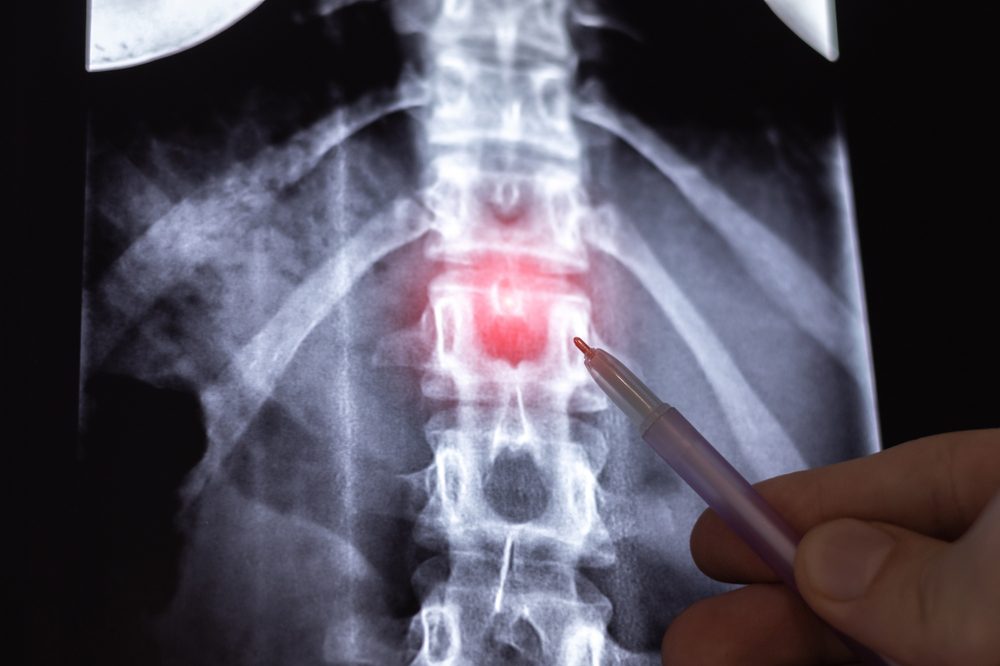

Diagnosing a Bulging Disc

Diagnosing a bulging disc or herniated disc involves a thorough evaluation by a healthcare professional. The process typically starts with a physical examination and a review of your medical history, focusing on pain patterns, muscle weakness, and any changes in reflexes. A physical therapist may perform specific tests to assess nerve function and mobility. To confirm the diagnosis and pinpoint the exact location and severity of the bulging disc, imaging studies such as MRI or CT scans are often recommended. Accurate diagnosis is essential for developing an effective treatment plan and addressing herniated disc symptoms.